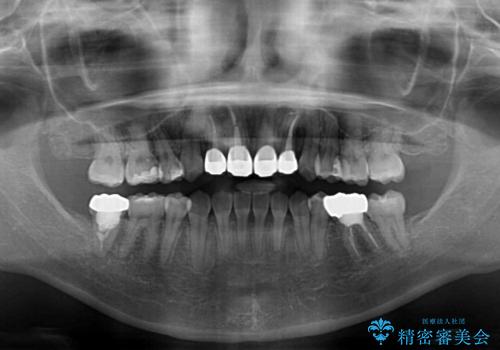

- 八重歯と前歯のデコボコ、開咬を気にして来院された患者様です。

抜歯矯正が必要であることはご自身で理解されており、目立たない装置をご希望であったので、上顎が裏側装置であるハーフリンガル装置にて治療を行うこととしました。

上顎前歯や下顎大臼歯に根管治療の必要な歯がいくつかあるため、矯正治療と並行して根管治療を行い、その後オールセラミッククラウンにて補綴治療を行うこととしました。

開咬の改善には舌突出癖を改善するためのトレーニングが必要ですが、しっかりと行っていただき、想定よりも早い期間で治療を終えることができました。